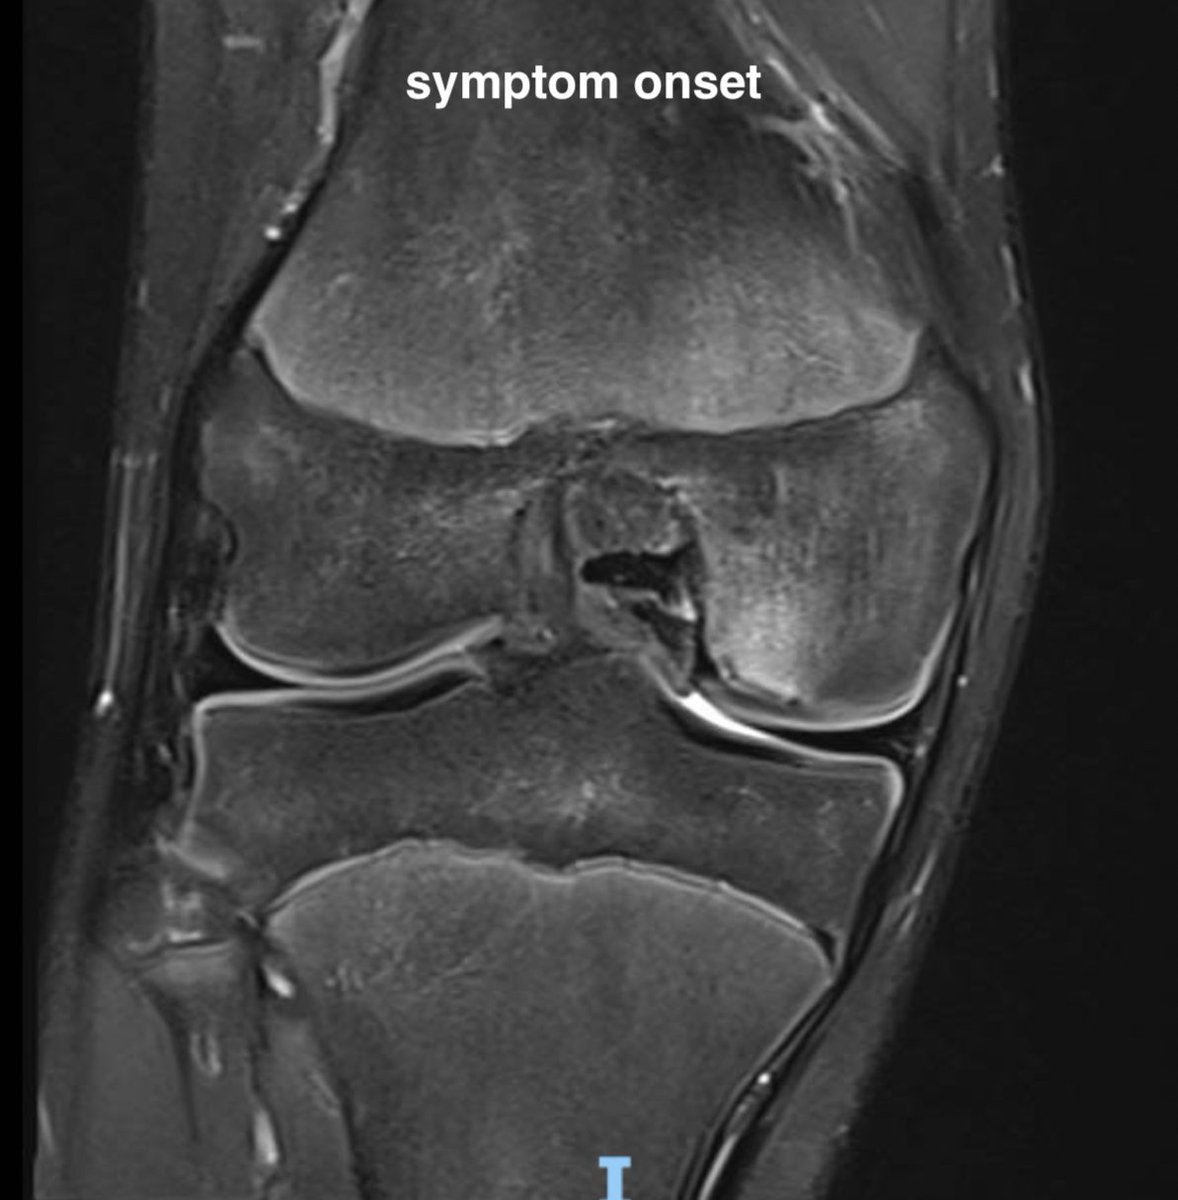

8. Subchondral insufficiency fracture (ex SONK!)

Older demographic, poor bone health risk factors, meds

? Hx of trivial injury eg step off steep kerb, turnstile

Typical to have meniscal tear associated

Effusion, deep bony pain on WB / impact